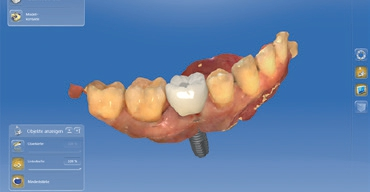

Zur optimalen Behandlungsplanung wurde neben dem DVT ein intraoraler Scan mit der CEREC Omnicam durchgeführt. Die vorhandenen Daten wurden sodann im Implantatplanungsprogramm (Galileos Implant, Dentsply Sirona) für die prothetische Planung sowie für das Design einer Bohrschablone mittels der CERECSoftware vorgenommen und zusammengeführt. Die Fertigung der Bohrschablone erfolgte binnen 45 Minuten direkt in der Praxis mit der Schleifeinheit CEREC MC XL Premium Package. Anschließend wurde die Titanhülse für die geführte Insertion eingeklebt (Abb. 4 bis 6).

Dabei nutzte ich das durch die provisorische Versorgung bereits bestehende Emergenzprofil des Weichgewebes für eine optimale definitive Versorgung. Etwaige okklusale Differenzen während der Einheildauer ließen sich auf diese Weise gut ausgleichen. Die finale Versorgung habe ich 2-teilig ausgeführt. Die Unterkonstruktion wurde mittels eines individuellen Zirkonabutments aus inCoris Meso Block gefräst und anschließend gesintert (CEREC SpeedFire). Die Krone wurde aus einem Celtra Duo LT Block geschliffen und im Anschluss individuell bemalt und glasiert (Abb. 18 bis 22).